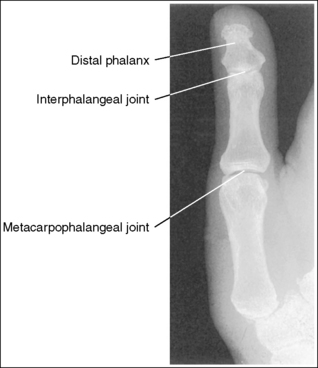

See Figures 4-12 and 4-13 and Box 4-5.

The first digit demonstrates an AP projection. The concavity on both sides of the phalangeal and metacarpal midshafts is equal, as is soft tissue width on both sides of the phalanges.

The IP, MP, and carpometacarpal (CM) joints are visible as open joint spaces, and the phalanges are not foreshortened.